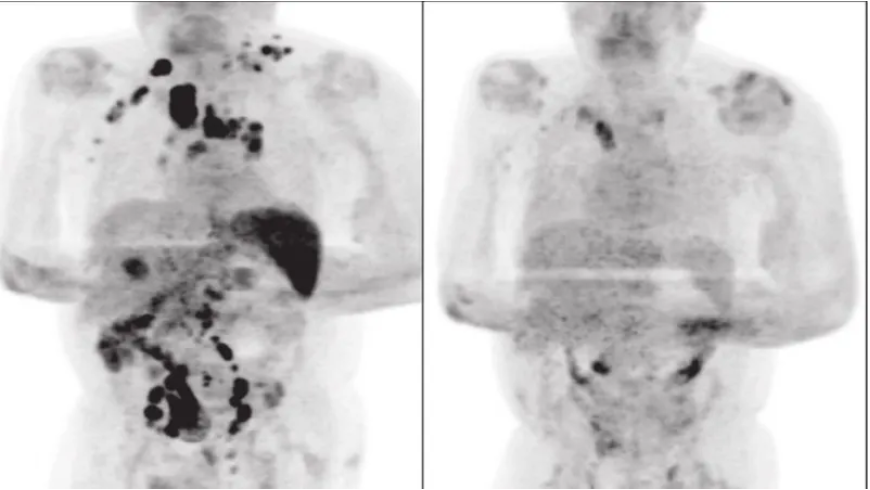

Cuatro meses después, un examen reveló una disminución generalizada del linfoma.

La hipótesis de los médicos es que la infección por Covid-19 desencadenó una respuesta inmunitaria antitumoral.